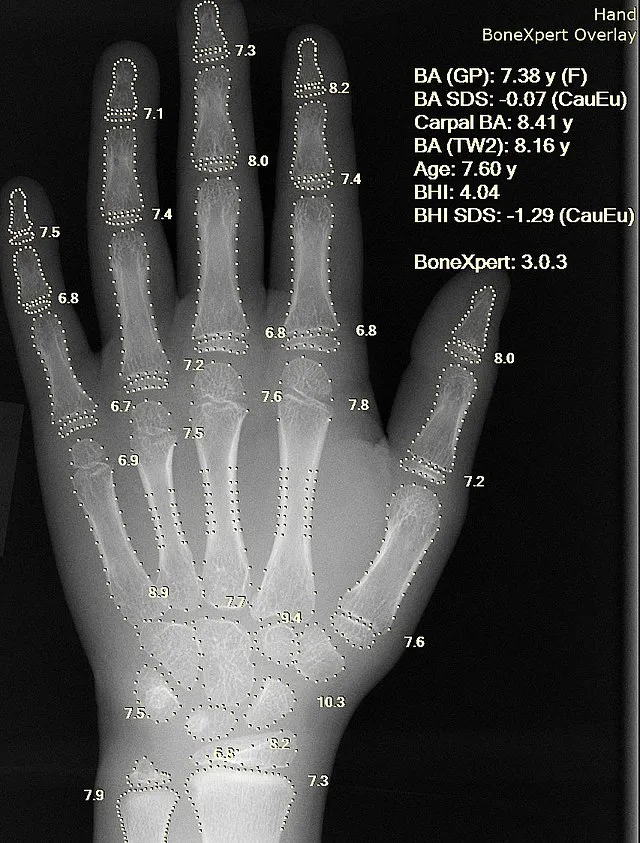

- Advanced bone age (X-ray hand/wrist).